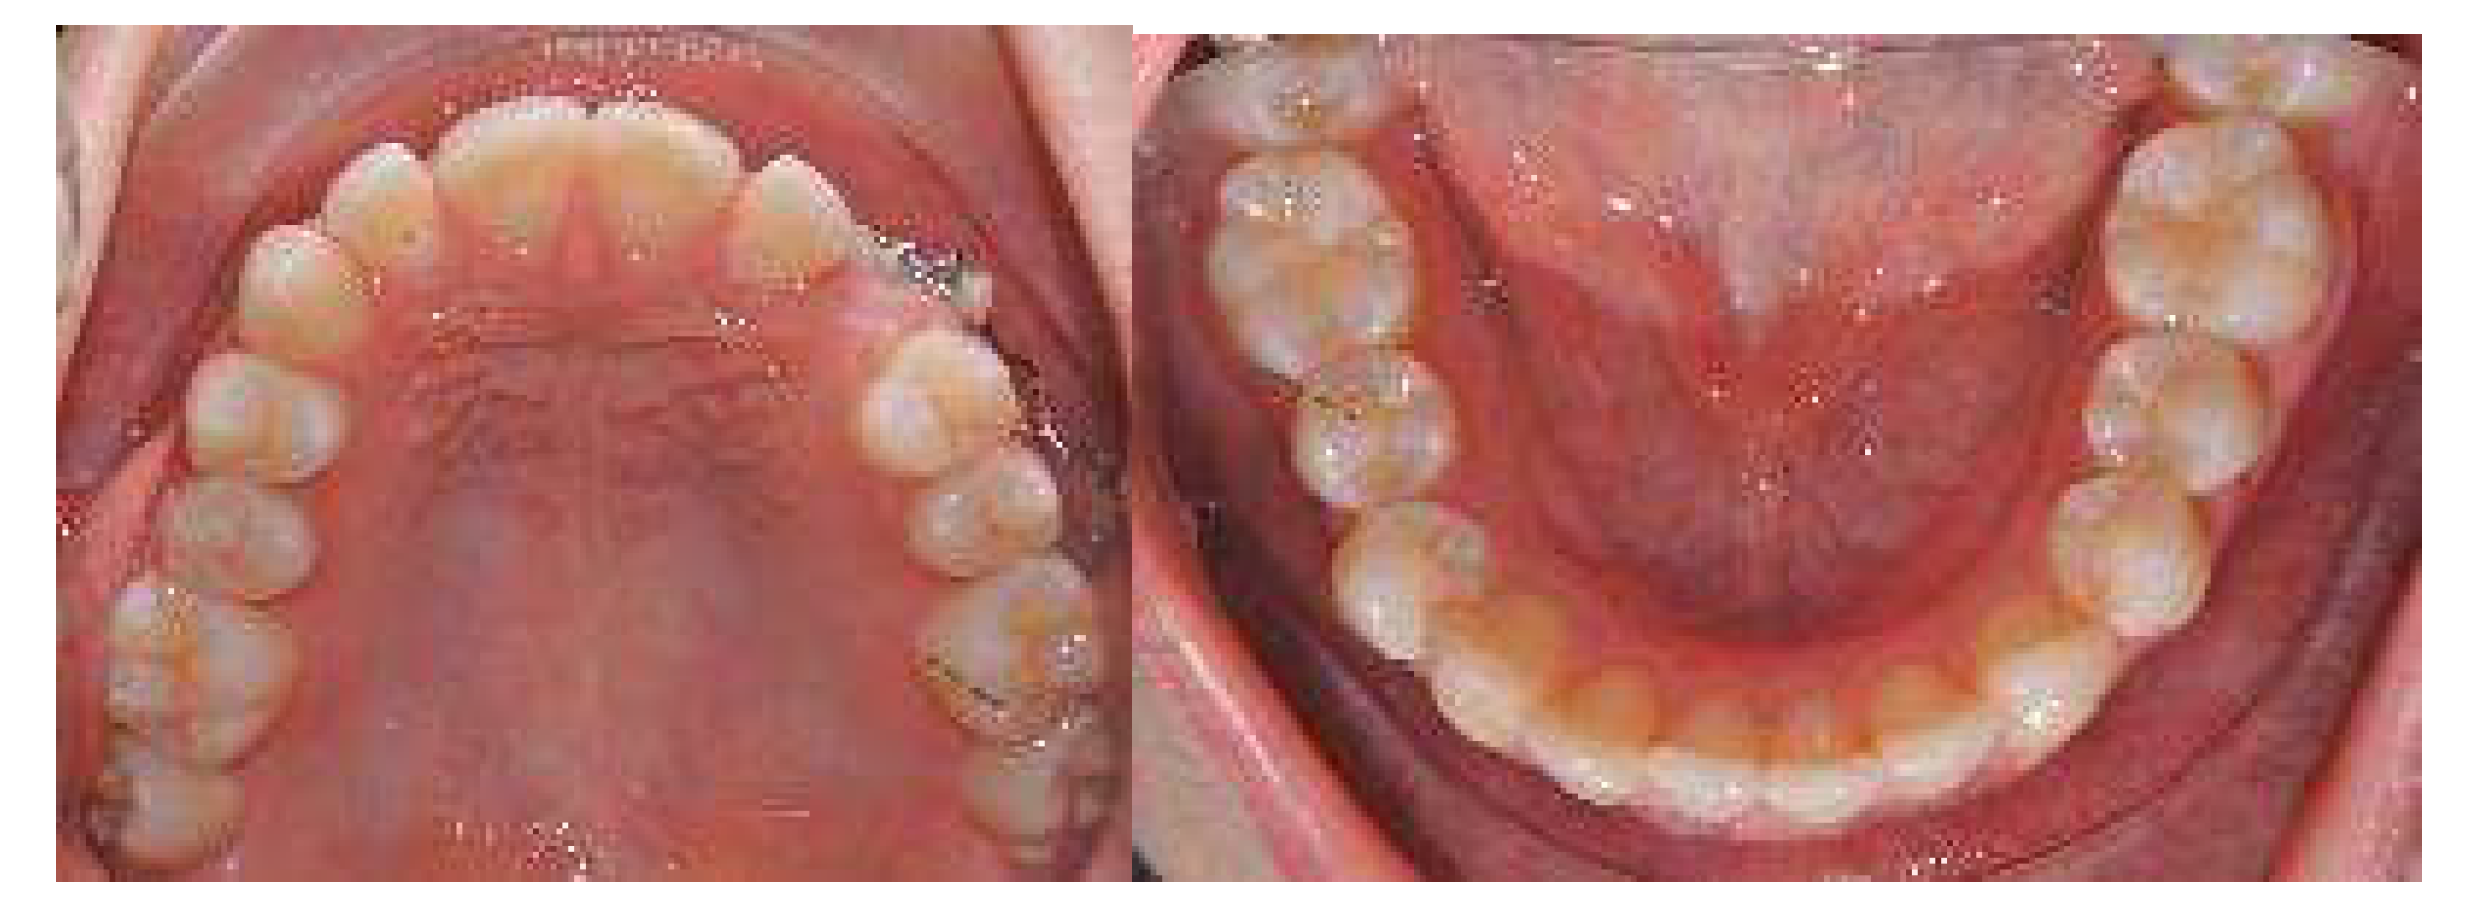

As for the palatally displaced canine, the cantilever spring was activated until the canine was visible and near the crest. Then, the deciduous canine was extracted and intraoral digital scans were taken by using the 3D scanner to start the orthodontic treatment (Figure 4).

Figure 4.

After 6 months of cantilever spring activation in extrusion and distalisation.

As for the palatally displaced canine, the cantilever spring was activated until the canine was visible and near the crest. Then, the deciduous canine was extracted, and intraoral digital impressions were taken for the clear aligner treatment.

Once the displaced tooth was in a better position and near the crest, intraoral impressions and a new series of pictures were taken. Then, an upper arch expansion was planned in order to correct the transverse discrepancy and crowding.